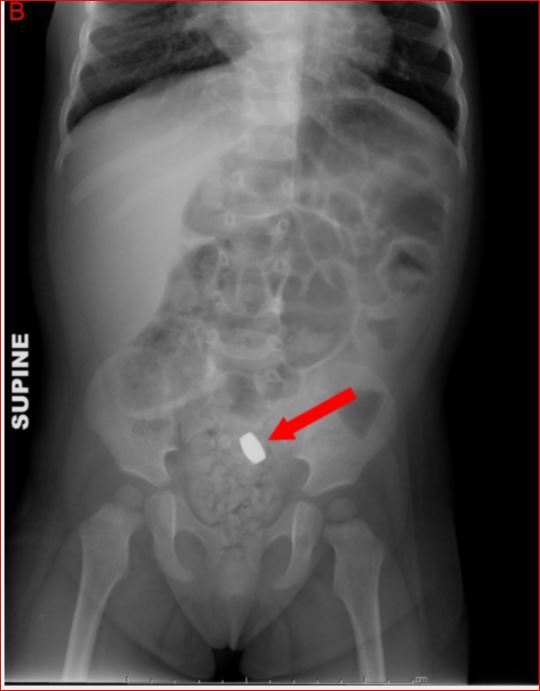

Second most common cause of small bowel obstruction?

Hernias

The presence of a tender, non-reducible mass in the hernia sac is consistent with an incarcerated hernia

In an incarierated hernia, a portion of the small bowel becomes trapped.

The associated edema can compromise blood flow, leading to ischemia and infraction (aka strangulation). this this is an condition requiring urgent surgical management.

How does small bowel obstruction present?

What are the commmon causes of SBO?

abdominal cramps, vomiting, high pitched bowel sounds and abdominal distention.

Post operative adhesions, hernias and tumors.